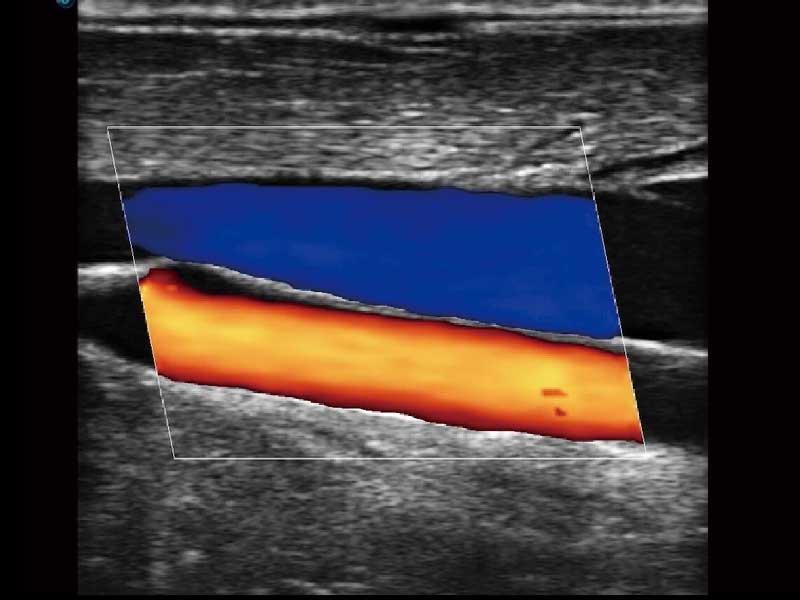

E2便携式彩色多普勒超声诊断系统采用专业的超声技术平台、高度集成化的硬件模块和结构设计、简便的操作流程、多探头接口设计,兼顾了优质图像、轻便机身以及台便两用的临床使用需求。

μ-Scan微米成像、空间复合成像、高分辨率血流成像。